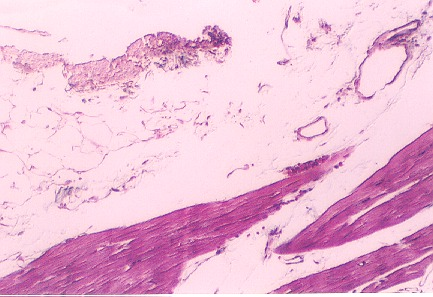

The myocardium is the actual wall of the heart containing the cardiac muscle itself. It is equivalent to the "tunica media" of the blood vessel. Scan the wall of the heart. The following photo shows cardiac muscle fibers in the wall. Note the branching fibers and the centrally located nuclei.

Identify the intercalated disks in this photo. What is their function?